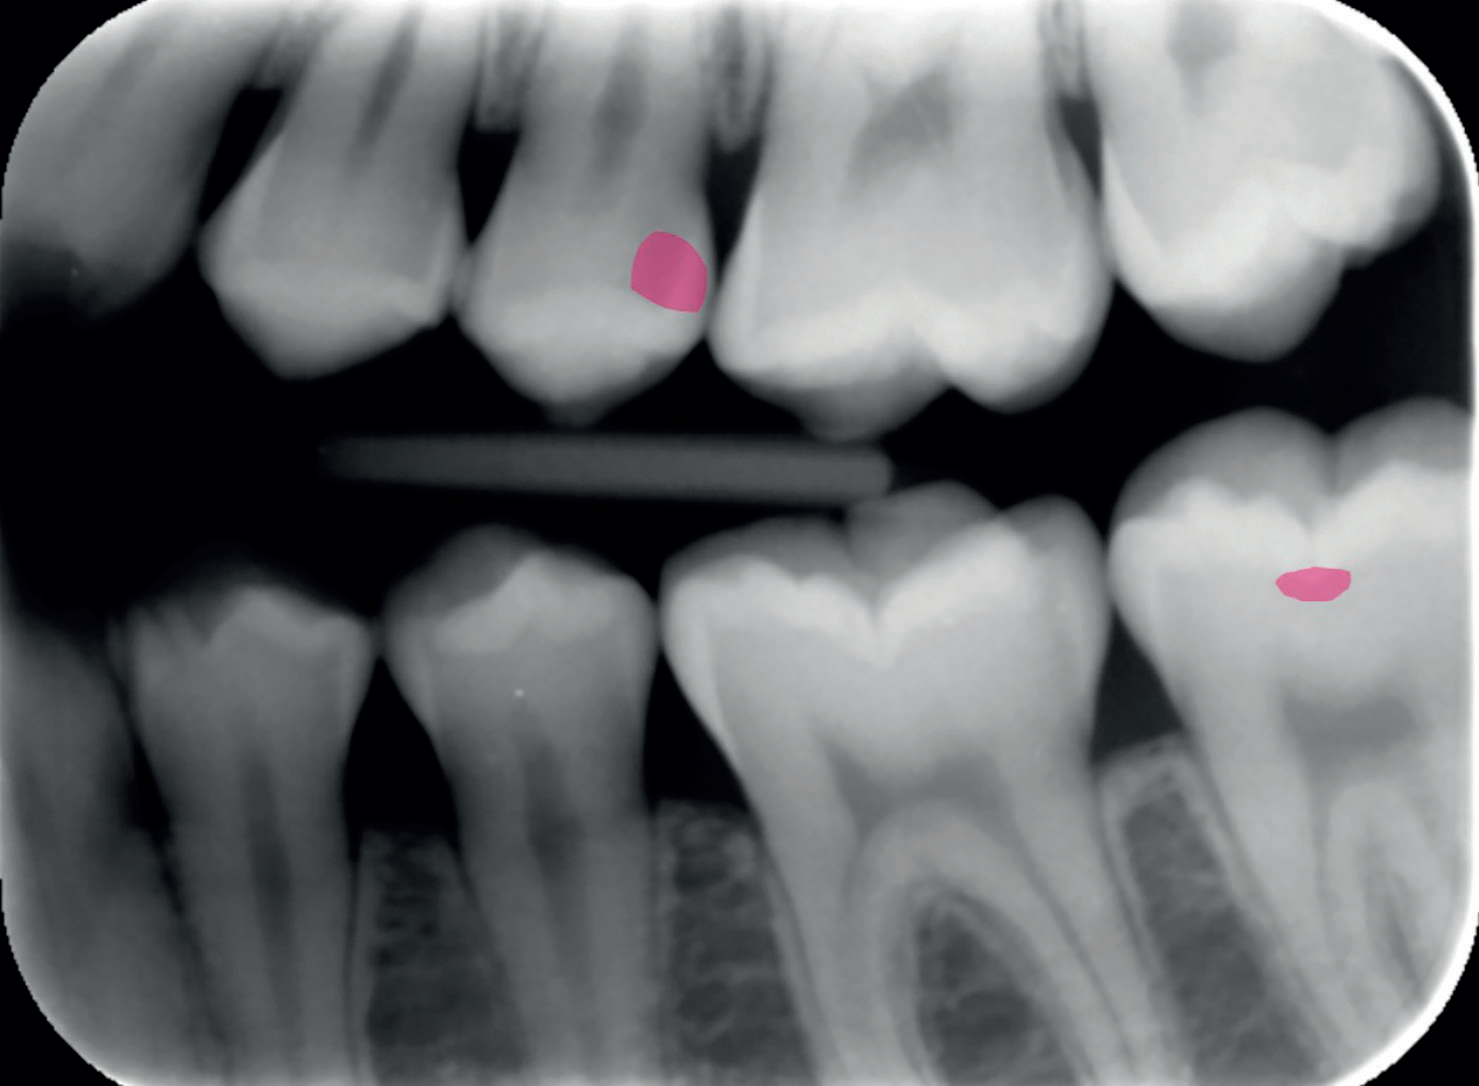

An X-ray confirmed the presence of a cavity, which was highlighted using a second-opinion AI software (Figures 1 and 2). Given the cavity’s location in the visible smile line and the patient’s age, I opted for a tooth-coloured filling rather than the NHS amalgam option. I chose Stela, a high-performance selfcure composite, for its aesthetic and functional qualities.

Figure 2: AI technology used to show areas of caries to the patient